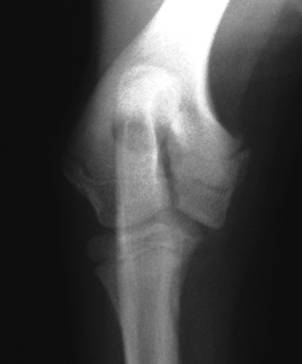

Salve in seguito ad una caduta ho riportato la frattura composta del trochite omerale dopo 30 gg di tutore alla visita l'ortopedico mi ha detto che posso toglire il tutore è prescritto 20 sedute di magnetofisioterapia spero di aver letto bene cosè. La frattura del trochite è probabilmente la frattura alla spalla più frequente, non è la più grave ma necessita di un inquadramento tempestivo, e sopratutto non ultimo chiaramente anche la decisione di un approccio chirurgico piuttosto che un approccio conservativo.

Il trochite omerale è essenziale per il movimento rotatorio della spalla. Solo un esame dello specialista ti può dire se hai problemi ai legamenti.cmq anni fà in seguito a caduta con la mtb da dh riportai la lussazione omerale con frattura del trochite.mi ripresi bene anche se ogni tanto cmq. Il trochite omerale è essenziale per il movimento rotatorio della spalla. D frattura del trochite omerale consolidata in posizione erronea che provoca impingment subacromiale. Home / shop / prodotti taggati fratture del trochite omerale. La frattura trochite omerale ad esempio interessa un osso specifico, appunto il trochite omerale. Il professor maiotti illustra le modalità di intervento possibili, dal trattamento non chirurgico all'alternativa della chirurgia quattro sono le strutture anatomiche principali: .appunto malleolo frattura trochite omerale hai eseguito una lastra alla spalla e il responso dice che hai avuto una frattura del trochite omerale? La testa omerale, il trochite, il trochine e la diafisi (figura 1). Frattura dell'omero significa rottura del braccio, si può verificare nella regione superiore, centrale o inferiore dell'osso. Fratture del trochite riduzione chirurgica delle fratture scomposte. Nel 2001 ho avuto la lussazione della spalla destra con frattura del trochite. Mi fecero tenere una fasciatura desault per 40 giorni, poi iniziai con i cicli di fisioterapia. In base alla sua entità e all'età del paziente, comporta seri e significativi problemi di movimento e guarigione. Fabrizio iannelli strumentisti gianpiero minghetti alfredo buscetto. Sclerosi trochite omerale è una. La cosa più lunga fu il recupero della mobilità articolare anche perchà.